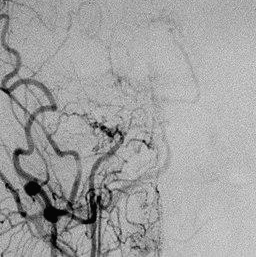

혈류가 감소돼 부족한 혈류량 공급을 위해 열린

미세혈관 모양이 연기가 피어오르는 모양과 비슷

하다고 하여 붙여진 이름입니다.

희귀 난치성 질환 중 하나이며 두개골의 경동맥이

막히거나 좁아져서 뇌로 가는 혈류를 감소시키고

부족한 혈류량을 공급하기 위해 생겨난 혈관으로

인해 발생 되는 질환입니다. 뇌에서 소형 뇌졸중,

뇌졸중 또는 출혈을 유발할 수 있습니다.